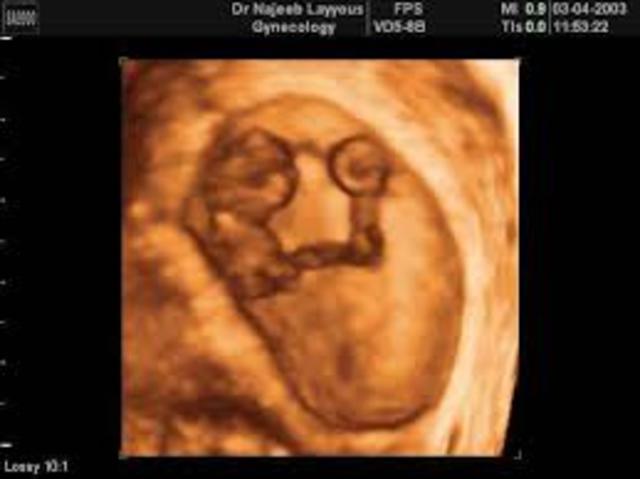

• Month 3

Month 3

The baby is the size of a olive. His or her fingers and toes are getting longer. The baby is now called a fetus no longer an embryo.